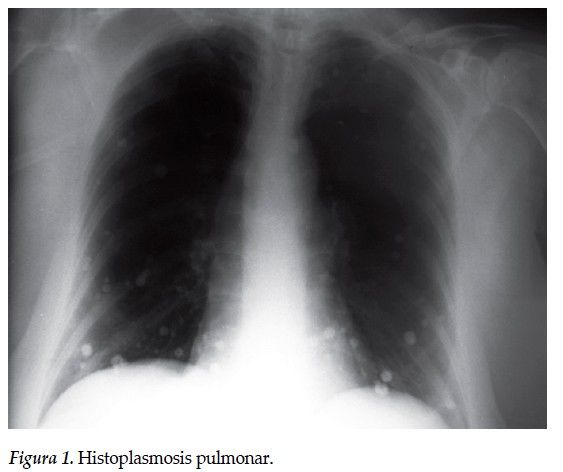

2. Clinica:Neumonitis persistente con infiltrados nodulares y cavitarios (95%) Sinusitis crónica (90%) Úlceras mucosas en nasofaringe (75%) Indicios de enfermedad renal (80%)